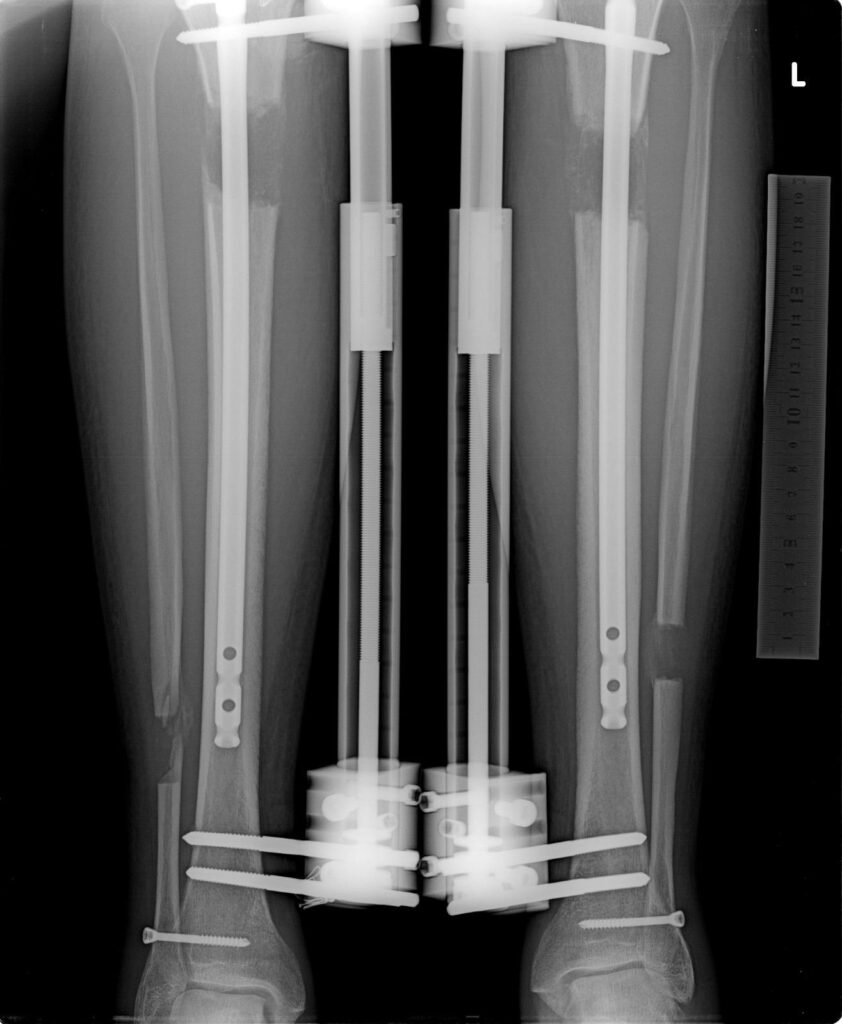

LON Method

Internal & External Combined

X-ray images showing the bone regeneration and consolidation phases during limb lengthening. The first image illustrates the gradual formation of new bone tissue, while the second highlights the fully consolidated bone.

LON Method: The LON method uses both external and internal fixation to achieve height increases of up to 7 cm (2.8 inches) in the tibia and 10 cm (4 inches) in the femur. After surgery, patients can walk with some limitations, supported by regular physiotherapy and specific exercises to maintain flexibility and strength. Most patients start walking without assistance within 4–5 months. By 6 months, most daily activities can be resumed, allowing patients to return to a more active lifestyle. Full recovery, including bone healing and the restoration of normal mobility, typically takes 9–12 months. This method also involves routine care for pin sites and wounds throughout the lengthening phase.